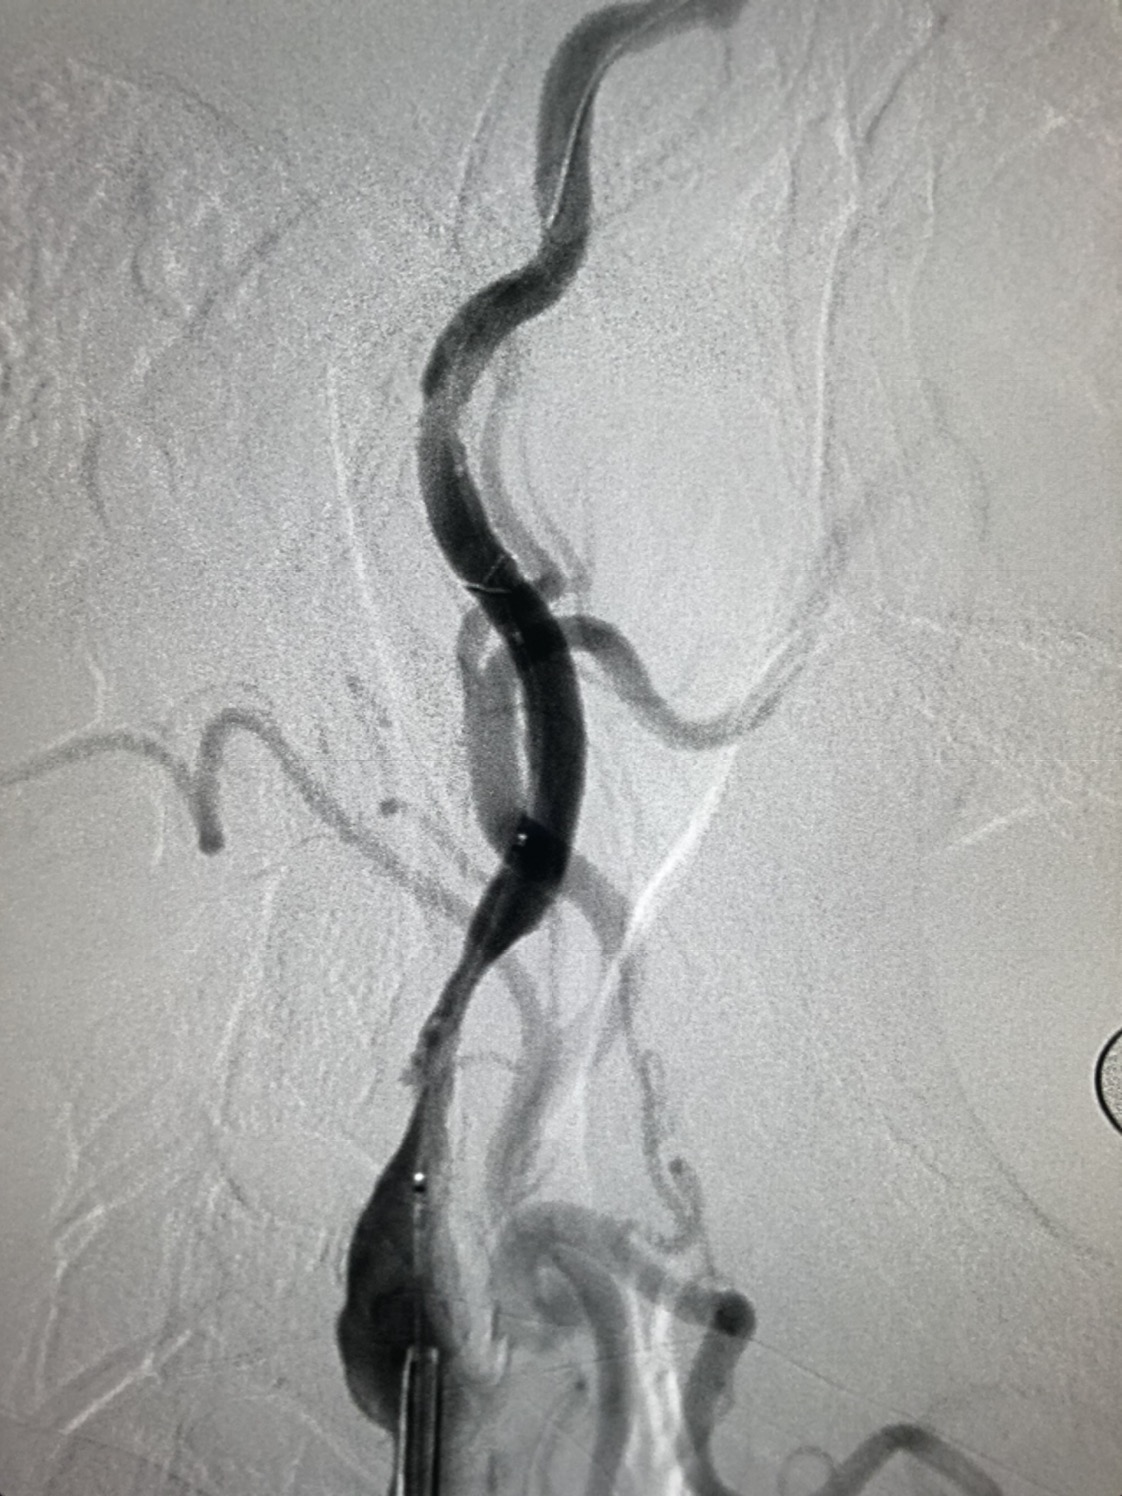

支架完全覆盖斑块,狭窄解除,支架形态柔顺贴合血管,无明显残余狭窄

术后颅内血供明显改善,胚胎型大脑后动脉显影良好。